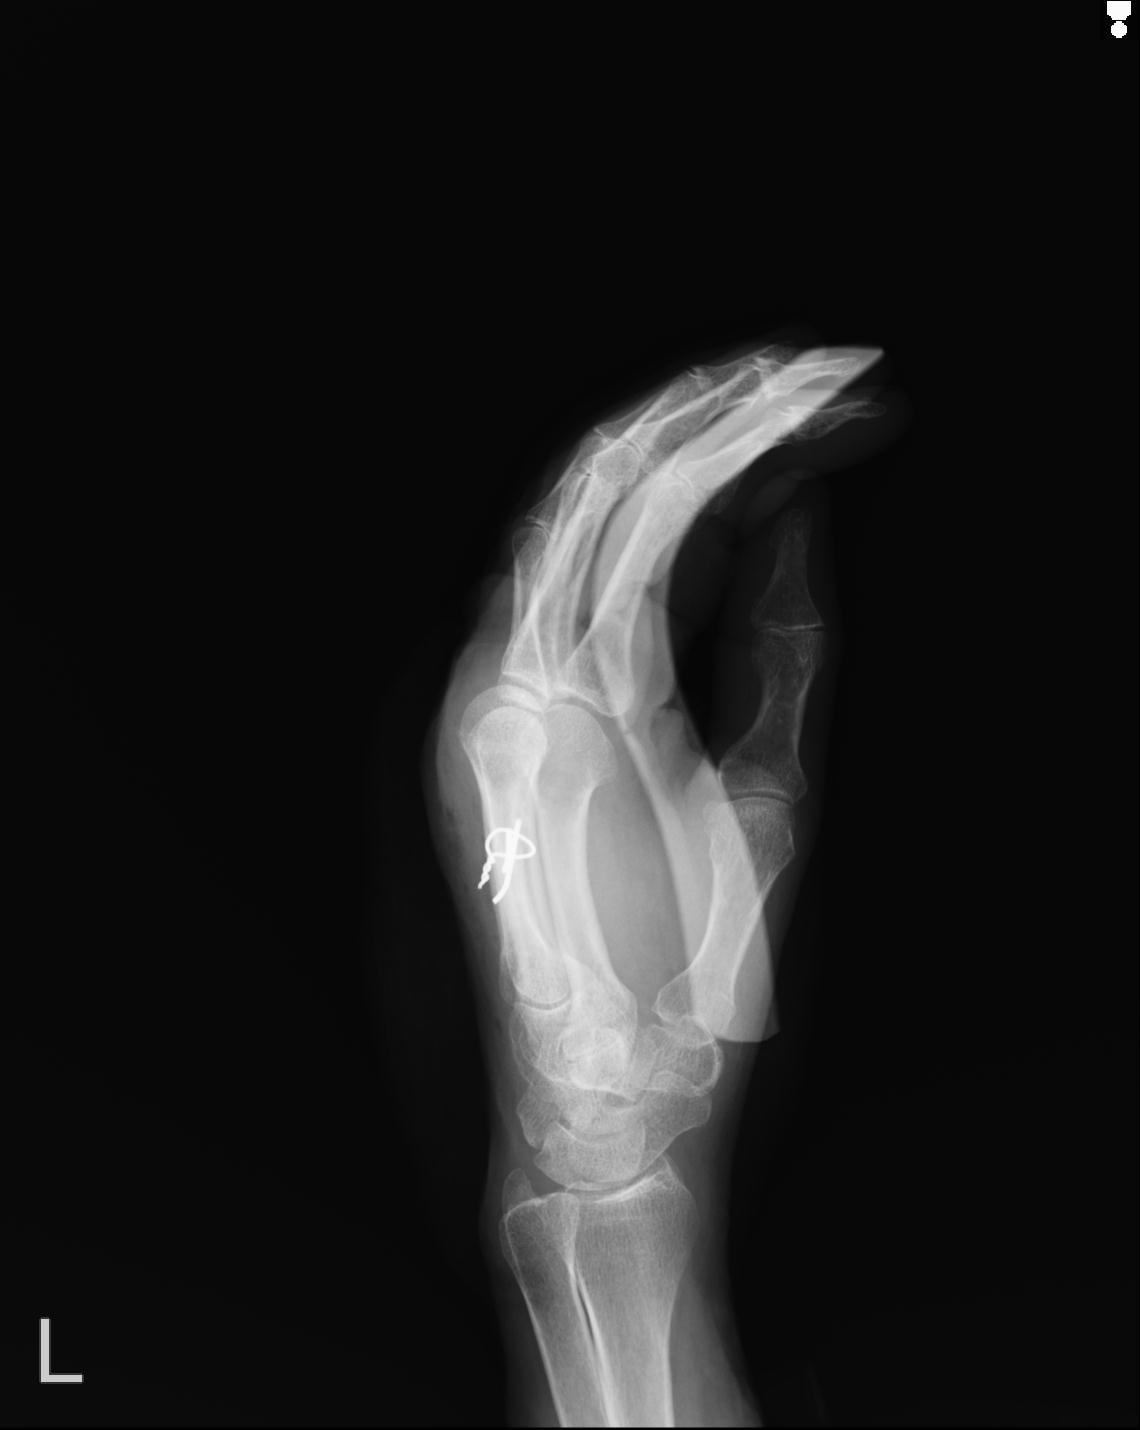

102860 1/21 (4R) 1/26 (4R) 3/15 左手 2R 91歳女性 左環指中節骨